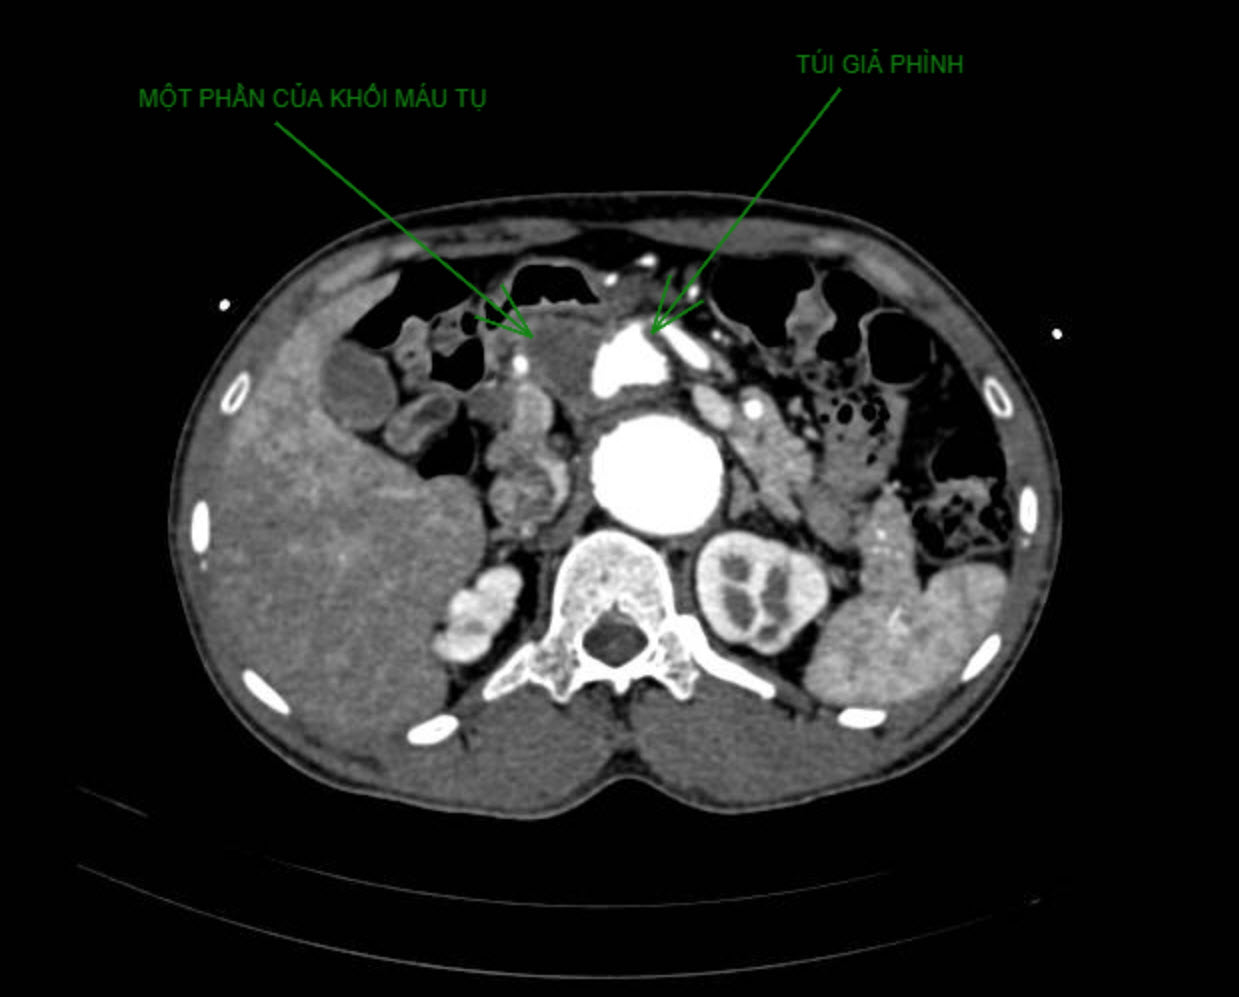

Sau can thiệp, người bệnh được theo dõi túi giả phình, nếu stent graft đạt hiệu quả chuyển dòng và tổ chức hóa khối máu tụ stent graft, túi giả phình sẽ giảm tự phát. Một ngày sau thủ thuật đầu tiên, người bệnh hết tình trạng tắc mật, các chỉ số sinh hóa (men gan, bilirubine toàn phần) hoàn toàn bình thường. Kết quả siêu âm kiểm tra cho thấy túi giả phình thu nhỏ lại chỉ còn đường kính 20mm. Tình trạng sức khỏe người bệnh ổn định, được cho xuất viện kèm thuốc huyết áp, kháng tiểu cầu kép và hẹn tái khám sau 2 tuần.

Vào ngày tái khám sau 2 tuần, tình trạng sức khỏe người bệnh ổn. Kết quả CT cho thấy giả phình thu hẹp đường kính còn 16 mm, hematoma giảm còn 40mm, stent graft đã đặt bình thường về dòng chảy và huyết động đồng thời vẫn ghi nhận dòng chảy tốc độ cao dọc theo mặt ngoài của stent vào trong túi giả phình. Với hi vọng giả phình và hematoma giảm theo thời gian, người bệnh được tiếp tục điều trị ngoại trú với thuốc huyết áp và thuốc kháng tiểu cầu đơn bằng clopidrogel (thay vì kháng tiểu cầu kép clopidrogel và aspirin).

Hình CT cho thấy khối máu tụ của người bệnh teo nhỏ sau can thiệp